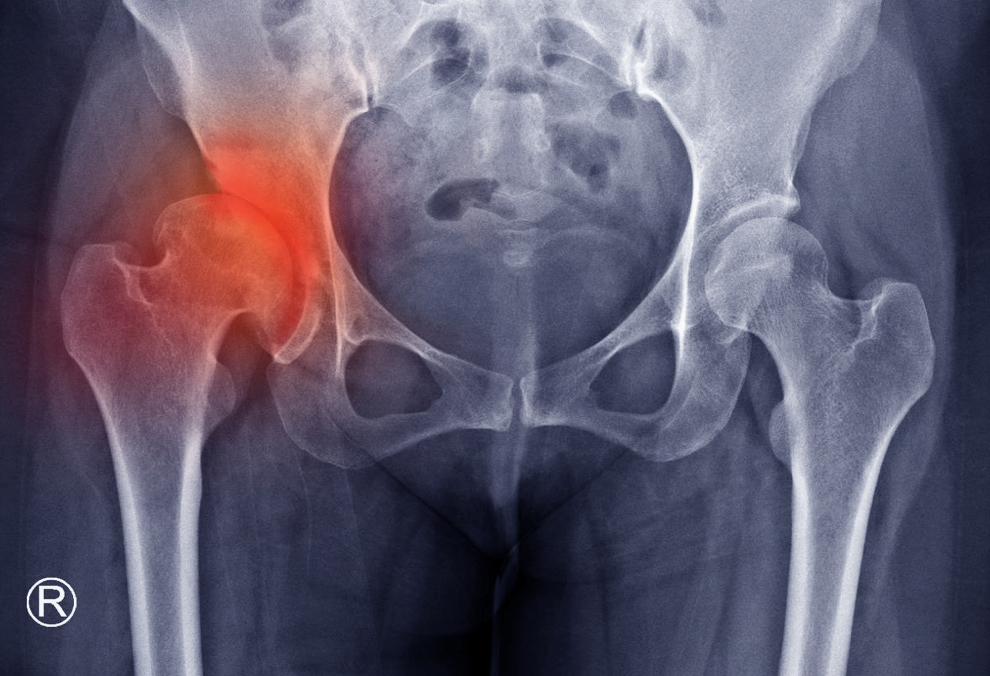

Đau hông là triệu chứng rất phổ biến, thường liên quan đến các vấn đề cơ xương khớp, dây thần kinh tọa hoặc căng cơ do vận động. Tuy nhiên, khi cơn đau hông trở nên dai dẳng, kéo dài và có tính chất bất thường, nó có thể là tín hiệu cảnh báo từ các khối u ác tính đang phát triển ở những cơ quan lân cận như buồng trứng, đại tràng, hoặc xương. Đối với nữ giới, vùng hông chậu là nơi tập trung của các cơ quan sinh sản, khiến họ càng cần phải nâng cao cảnh giác với các cơn đau này.

Nếu cơn đau hông của bạn xuất hiện mà không hề có chấn thương hay vận động quá sức nào trước đó, và có xu hướng tăng cường độ theo thời gian thay vì thuyên giảm, đây là một dấu hiệu cảnh báo cần được kiểm tra.

Cơn đau hông này có thể là do ung thư buồng trứng hoặc ung thư tử cung đang phát triển lớn, chèn ép các dây thần kinh và mô xung quanh vùng chậu và hông. Ở nữ giới, khối u buồng trứng thường lan rộng âm thầm, gây ra đau hông khi nó bắt đầu xâm lấn các cấu trúc lân cận. Tương tự, ung thư đại trực tràng ở vị trí sigma hoặc trực tràng cũng có thể gây đau lan xuống vùng hông. Cần lưu ý, đau hông do ung thư thường không thuyên giảm khi nghỉ ngơi hoặc dùng thuốc giảm đau cơ xương khớp thông thường.